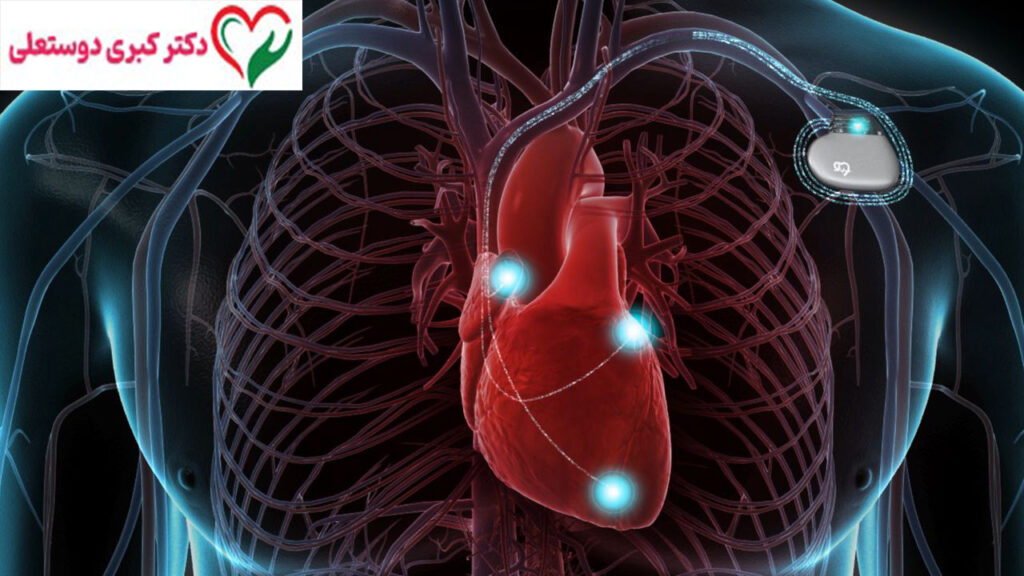

ICD (Implantable Cardioverter Defibrillator) دستگاهی الکترونیکی و کوچک است که در داخل بدن بیمار، معمولاً زیر پوست قفسه سینه یا زیر ترقوه، کاشته می‌شود. این دستگاه به‌طور مداوم ریتم قلب را پایش می‌کند و در صورت تشخیص ریتم‌های خطرناک، به‌صورت خودکار وارد عمل می‌شود.

ICD چگونه کار می‌کند؟

ICD از سه بخش اصلی تشکیل شده است:

1. ژنراتور (باطری و مدار الکترونیکی)

2. الکترودها (سیم‌هایی که به قلب متصل می‌شوند)

3. نرم‌افزار هوشمند تشخیص ریتم قلب

این دستگاه ریتم قلب را لحظه‌به‌لحظه بررسی می‌کند. اگر ریتم‌های خطرناکی مانند:

تشخیص داده شوند، ICD یکی از اقدامات زیر را انجام می‌دهد:

• ارسال پالس‌های سریع برای اصلاح ریتم

• یا وارد کردن شوک الکتریکی نجات‌بخش